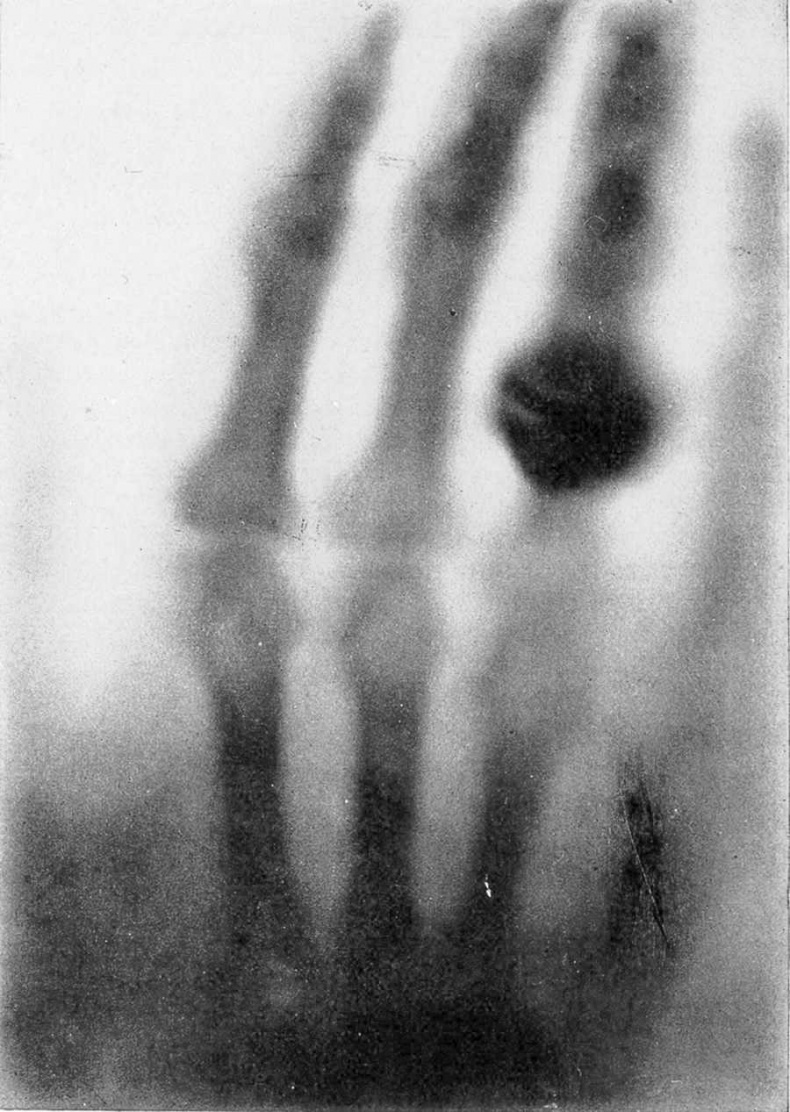

Взгляд внутрь организма, 1895 год. Первый рентгеновский снимок, рука г-жи Рентген. Публикуется с разрешения Национальной медицинской библиотеки Национальных институтов здравоохранения США.